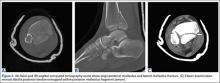

A 67-year-old man slipped and fell on ice while jogging and subsequently presented to the emergency department with a closed bimalleolar ankle fracture-dislocation. Plain radiography (Figure 1) and computed tomography (CT) showed an oblique lateral malleolar fracture and a large posterior malleolar fracture. Further examination of the CT scan revealed entrapment of the tibialis posterior tendon within the posterior malleolar fracture (Figure 2).